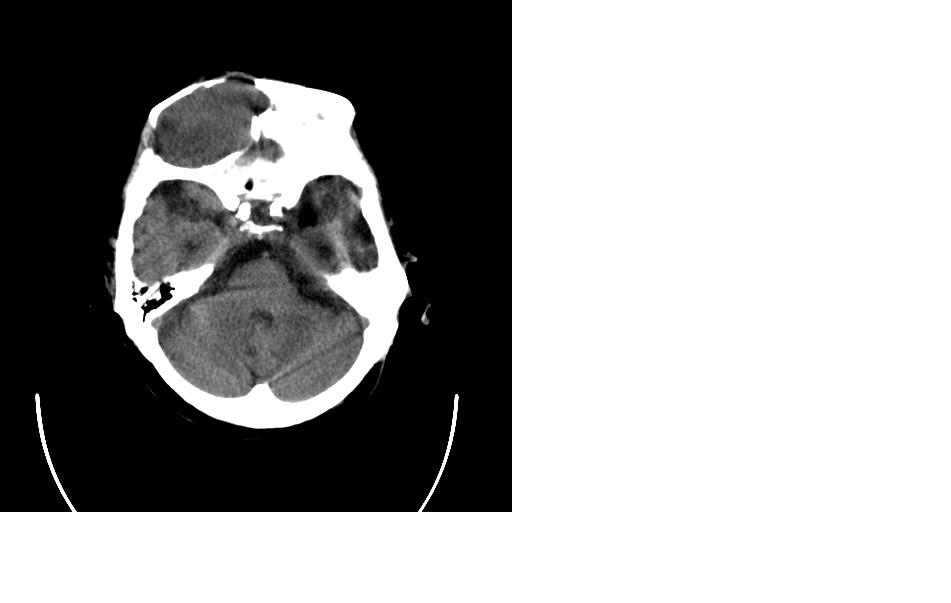

女,77岁,渐进性突眼2年,无其他明显症状

病变位于起源于右侧筛窦,右侧眼球受压移位,右侧大脑半球额叶白质受压塌陷,水肿不明显.额骨呈压迫性骨质吸收变薄.考虑脑膜瘤,建议增强吧

右侧额部软组织密度肿块,界限不清,明显向前下方增长,占位效应明显,内见钙化,局部颅骨明显吸收.考虑:右额叶脑膜瘤.建议:增强

右额窦粘液囊肿,向前累及筛窦并进入眼眶使眼球前突;向下进入颅内右额叶脑质及侧脑室受压

病变应起源于右侧额窦/或额骨板障,肿块周围骨包壳尚完整,呈膨胀挤压改变,右侧眼球受压移位,右侧大脑半球额叶白质受压塌陷,水肿不明显.考虑为良性病变,骨纤维瘤/或骨嗜酸性肉芽肿? 建议增强吧

支持:病变的起源我乐意定在右额窦。右额窦粘液囊肿或粘液腺癌累及筛窦、眼眶使眼球前突;向下进入颅内右额叶脑质及侧脑室受压变形。

额骨右侧呈明显膨胀性骨质破坏,内外板明显变薄.考虑骨巨细胞瘤或动脉瘤样骨囊肿的可能性大。

定位:来源右额窦。定性:良性占位—额窦黏液囊肿。理由1、病灶中心位于右额窦区,侵及筛窦并向下向前压迫眼球2、骨质呈膨胀性改变,骨质弓形变薄但骨壳完整,如为恶性骨质应为侵蚀性破坏3、黏液囊肿好发于筛窦、额窦。